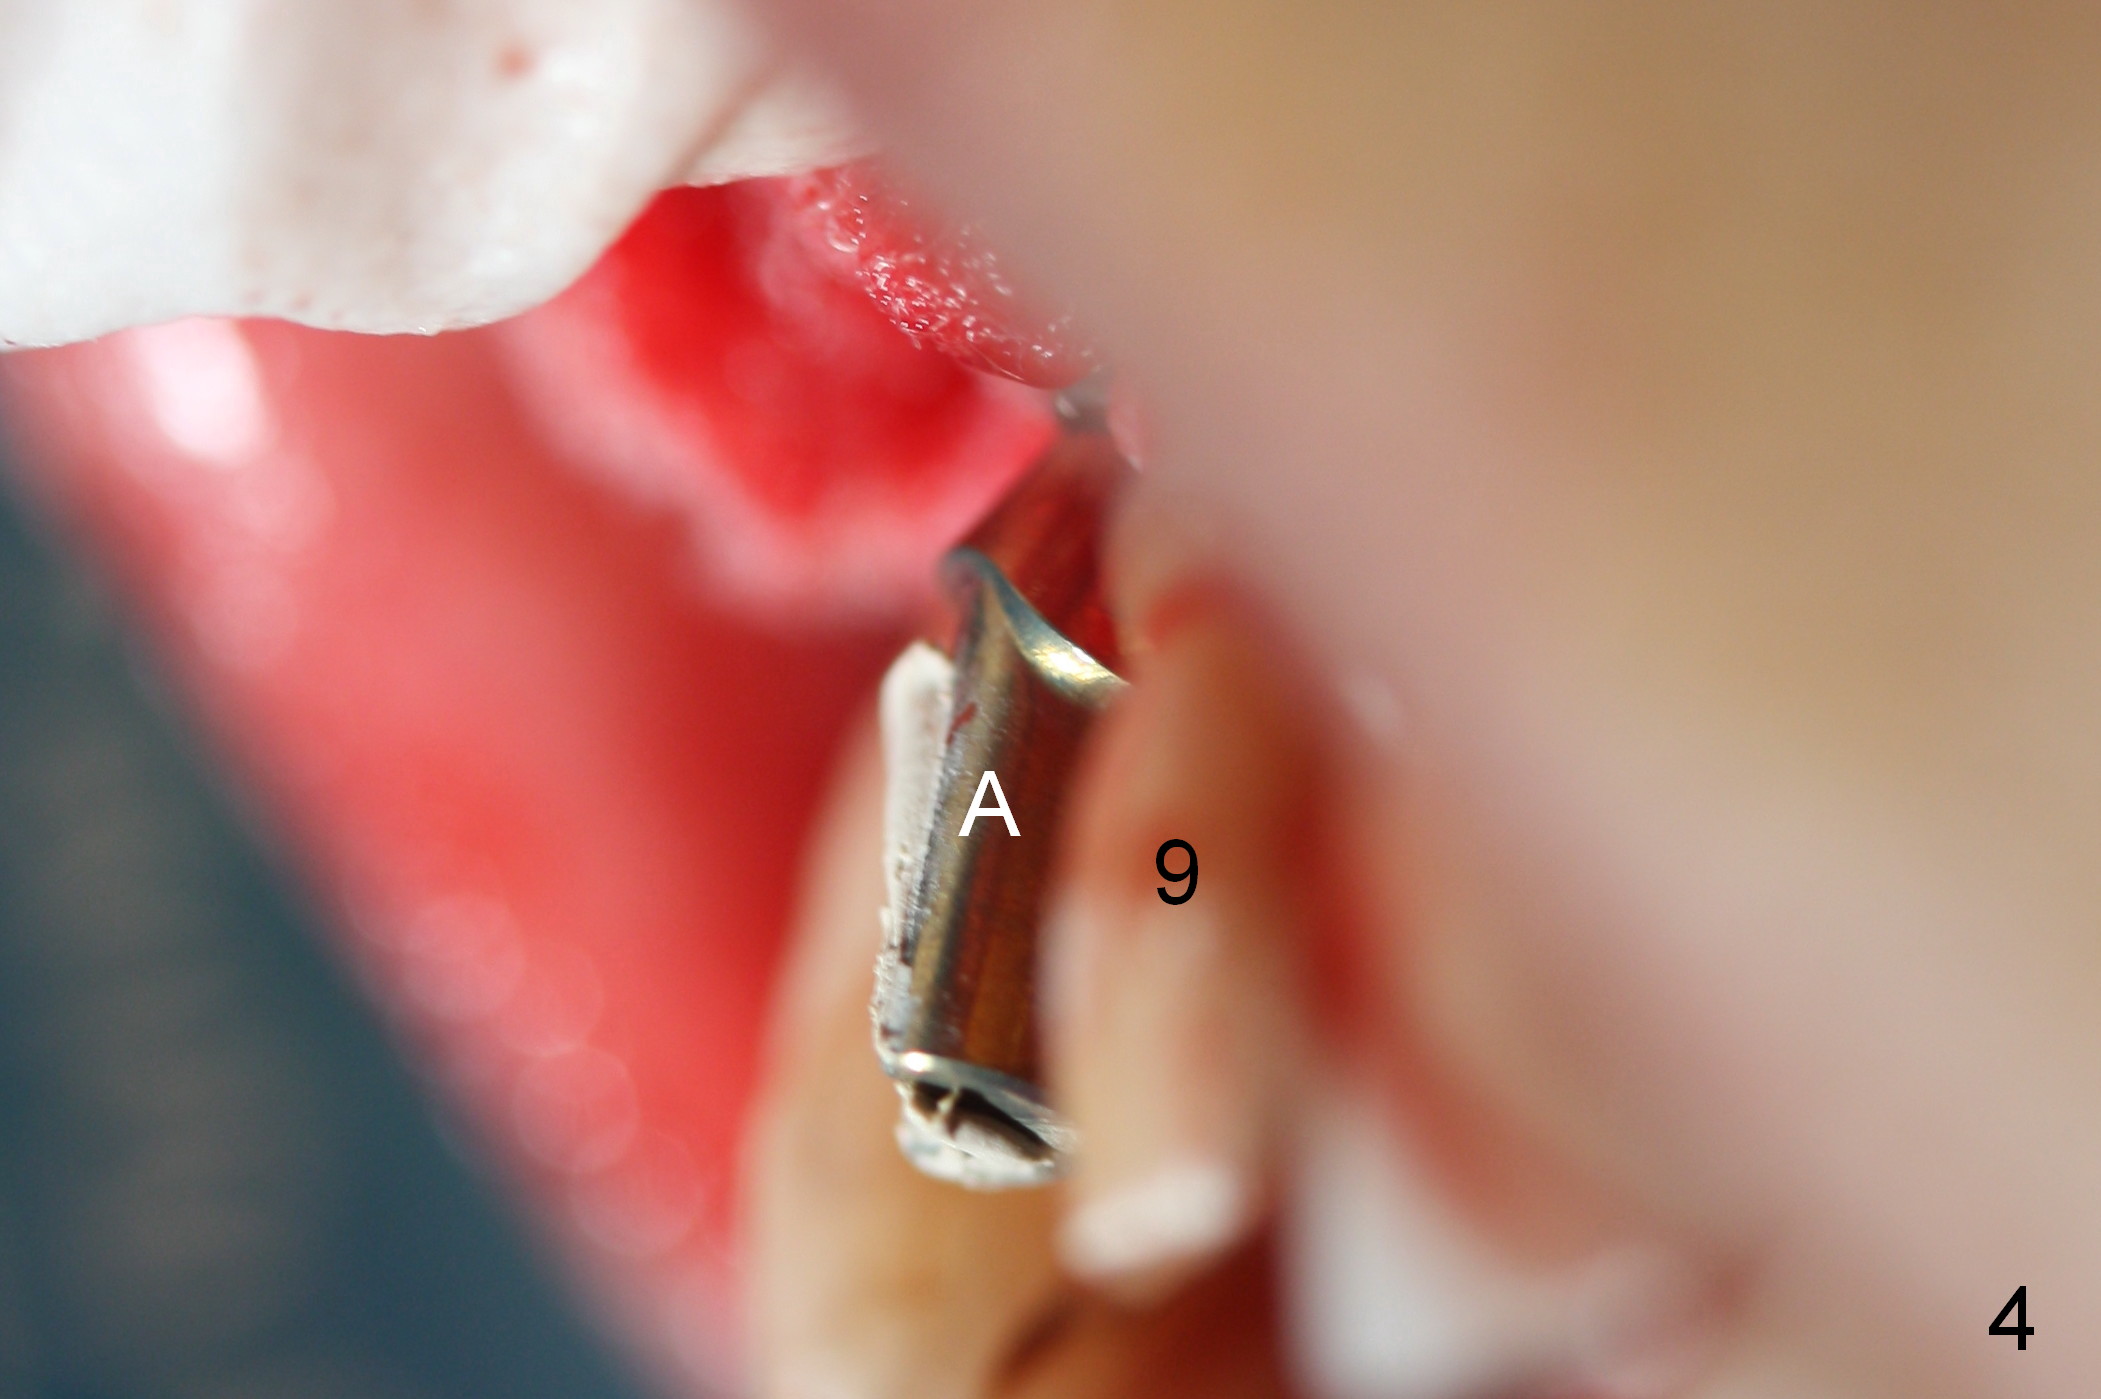

The patient returns for Zirconium abutment retrieval 1 month post its fracture.  When the provisional is removed, the gingival pontic morphology remains (Fig.2).  There is no problem to remove the abutment screw (Fig.1 with its driver), whereas it is difficult to remove the remaining abutment (Fig.2 *) due to limited access.  When the access improves by incision (Fig.3), buccal implant thread exposure is confirmed and the fractured abutment (*) is to be removed easily.  A 15° angled abutment (A) corrects the angulation, but not the position (Fig.4,5, compare to Fig.1 with a driver in place).  After being trimmed, the labial contour of the abutment is equivalent to that of #9 (Fig.6,7), but the margin is higher.  Using an abutment with taller gingival height (from 2 mm to 3 mm) may alleviate the margin issue.